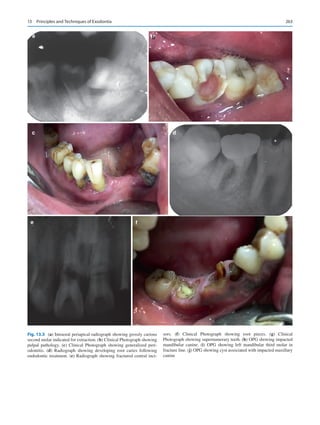

icine man for their healthcare. Direct to consumer marketing

of healthcare tools such as genetic testing is already preva-

lent in many countries. Several patients are aware of which

chemotherapy may be best effective for the management of

1  Oral and Maxillofacial Surgery in India: How Did We Get Here and Where Are We Going?

6

their cancers even before they see their doctor, today. Where

does that place a specialist in the future?